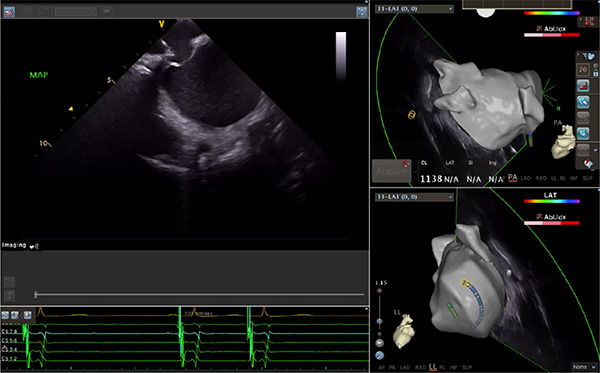

超聲心動(dòng)圖技術(shù)包括常規(guī)經(jīng)胸超聲(TTE)、經(jīng)食管超聲(TEE)、心腔內(nèi)超聲(ICE)、超聲聲學(xué)造影(MCE)、三維超聲心動(dòng)圖等,ICE是一種新興技術(shù)——將微型的換能器安裝在心導(dǎo)管的尖端,經(jīng)由外周血管輸送至心腔內(nèi)部,換能器發(fā)射聲波,對心臟及其鄰近組織進(jìn)行實(shí)時(shí)高質(zhì)量成像和(或)血流動(dòng)力學(xué)測定的超聲成像技術(shù)?;诓煌募夹g(shù)原理,心腔內(nèi)超聲導(dǎo)管被分為兩類:機(jī)械旋轉(zhuǎn)式超聲導(dǎo)管和相控陣超聲導(dǎo)管。目前,臨床上主要應(yīng)用的是相控陣超聲導(dǎo)管,ICE成像通過術(shù)者旋轉(zhuǎn)導(dǎo)管及操縱導(dǎo)管手柄上的兩個(gè)旋鈕來完成。

ICE門檻高、集成了超聲和圖像處理最前端的技術(shù),是當(dāng)前內(nèi)窺超聲方向最挑戰(zhàn)的領(lǐng)域。不同于傳統(tǒng)接觸式三維重建方法會(huì)產(chǎn)生假腔,影響術(shù)者對靶點(diǎn)或結(jié)構(gòu)的判斷,心腔內(nèi)超聲(ICE)可直接顯示心臟結(jié)構(gòu),有助于理解心臟內(nèi)各部位之間的解剖關(guān)系,不僅具有實(shí)時(shí)成像、并發(fā)癥監(jiān)測以及良好的耐受性,同時(shí)以股靜脈入路,無需全麻或深度鎮(zhèn)靜,日益成為心臟介入手術(shù)中重要輔助工具,被譽(yù)為心臟介入醫(yī)生的“黃金眼”。心腔內(nèi)超聲可用于多種心臟介入手術(shù),潛在患者群體龐大,動(dòng)脈網(wǎng)測算我國心腔內(nèi)超聲導(dǎo)管市場空間或?qū)⒊?00億元,具有廣闊前景。

隨著心腔內(nèi)超聲的應(yīng)用更廣,性能也在逐漸優(yōu)化,已從二維成像轉(zhuǎn)變?yōu)?strong>三維成像,極大增強(qiáng)了引導(dǎo)及可視化能力。二維心腔內(nèi)超聲支持雙平面或三平面成像,可顯示兩個(gè)或三個(gè)不同的平面視圖,但醫(yī)生需將這些圖像在腦海中重新構(gòu)建為三維解剖結(jié)構(gòu)。三維心腔內(nèi)超聲則可直接呈現(xiàn)三維解剖結(jié)構(gòu)圖,便于醫(yī)生更輕松地開展手術(shù)。按照產(chǎn)品發(fā)展方向,預(yù)計(jì)心腔內(nèi)超聲還將向更清晰、精準(zhǔn)、多功能等方向發(fā)展。